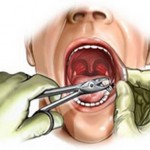

Hier, j’avais donc rendez-vous avec mon jeune et compétent chirurgien-dentiste italien et son assistance tout aussi affable.

Le menu était chargé : arrachage d’une dernière dent et pose du premier implant.

L’arrachage de la dent, pas de réel problème.

Il faut dire que je commence à être un vieux routier en cette matière.

La pose de l’implant dentaire fut plus aventureuse.

Un premier essai en position antérieure.

Essai manqué !

La masse osseuse disponible s’avère finalement plus chiche qu’annoncée par la radiographie, et donc insuffisante.

Cette localisation serait trop risquée.

D’où, rebelote en position plus postérieure.

Cela me parut interminable.

Mes muscles masséters et temporo-pariétaux n’en pouvaient plus d’être aussi longtemps sollicités.